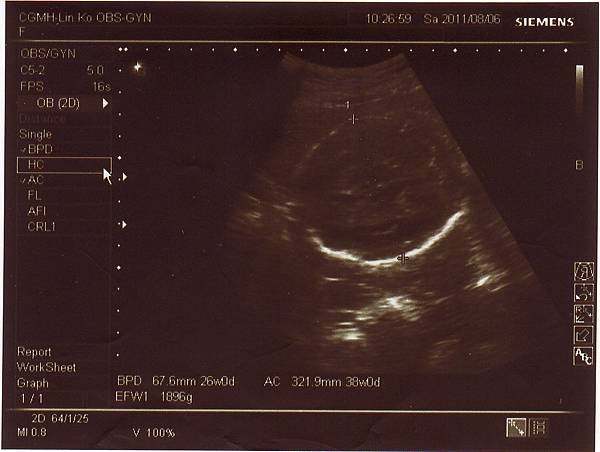

2011.08.06 26週 例行性產檢

終於今天產檢,問了醫生寶寶大小,

醫生說大約九百多克,和同期的寶寶比起來重量也不輕,

而兔妹妹的發展也符合懷孕週數,